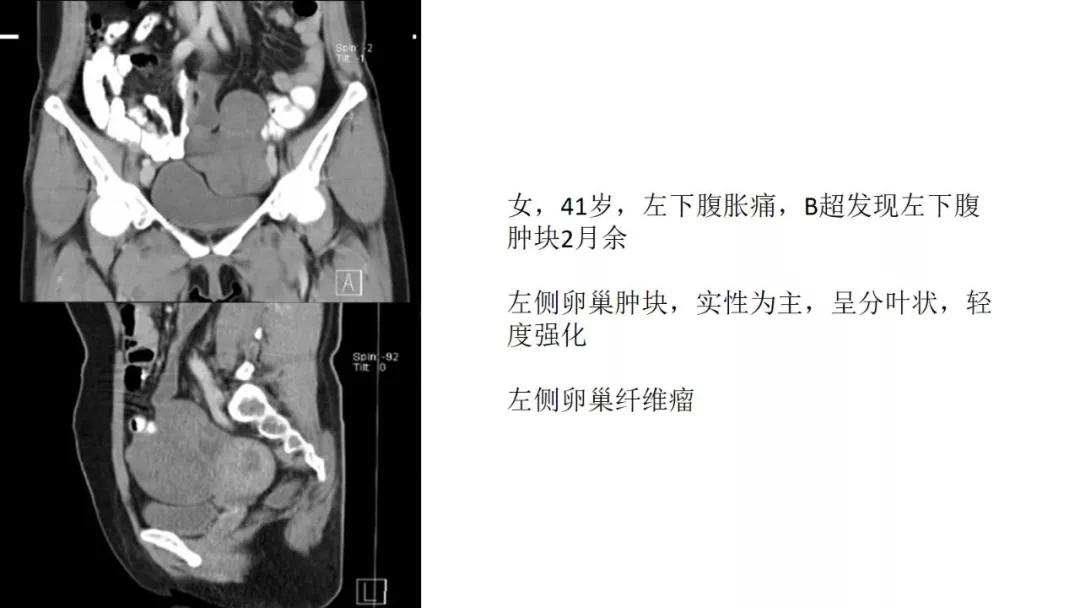

性索间质性肿瘤:较少见,良性多,多数肿瘤具有内分泌功能,可伴有内分泌症状及子宫内膜增生,内膜癌,乳腺疾病。多呈囊实性及实性肿块,界清,形态规则或欠规则,少有壁结节,多数呈实性伴有大片变性低密度改变,轻中度强化。

病理:左侧卵巢卵泡膜-纤维瘤